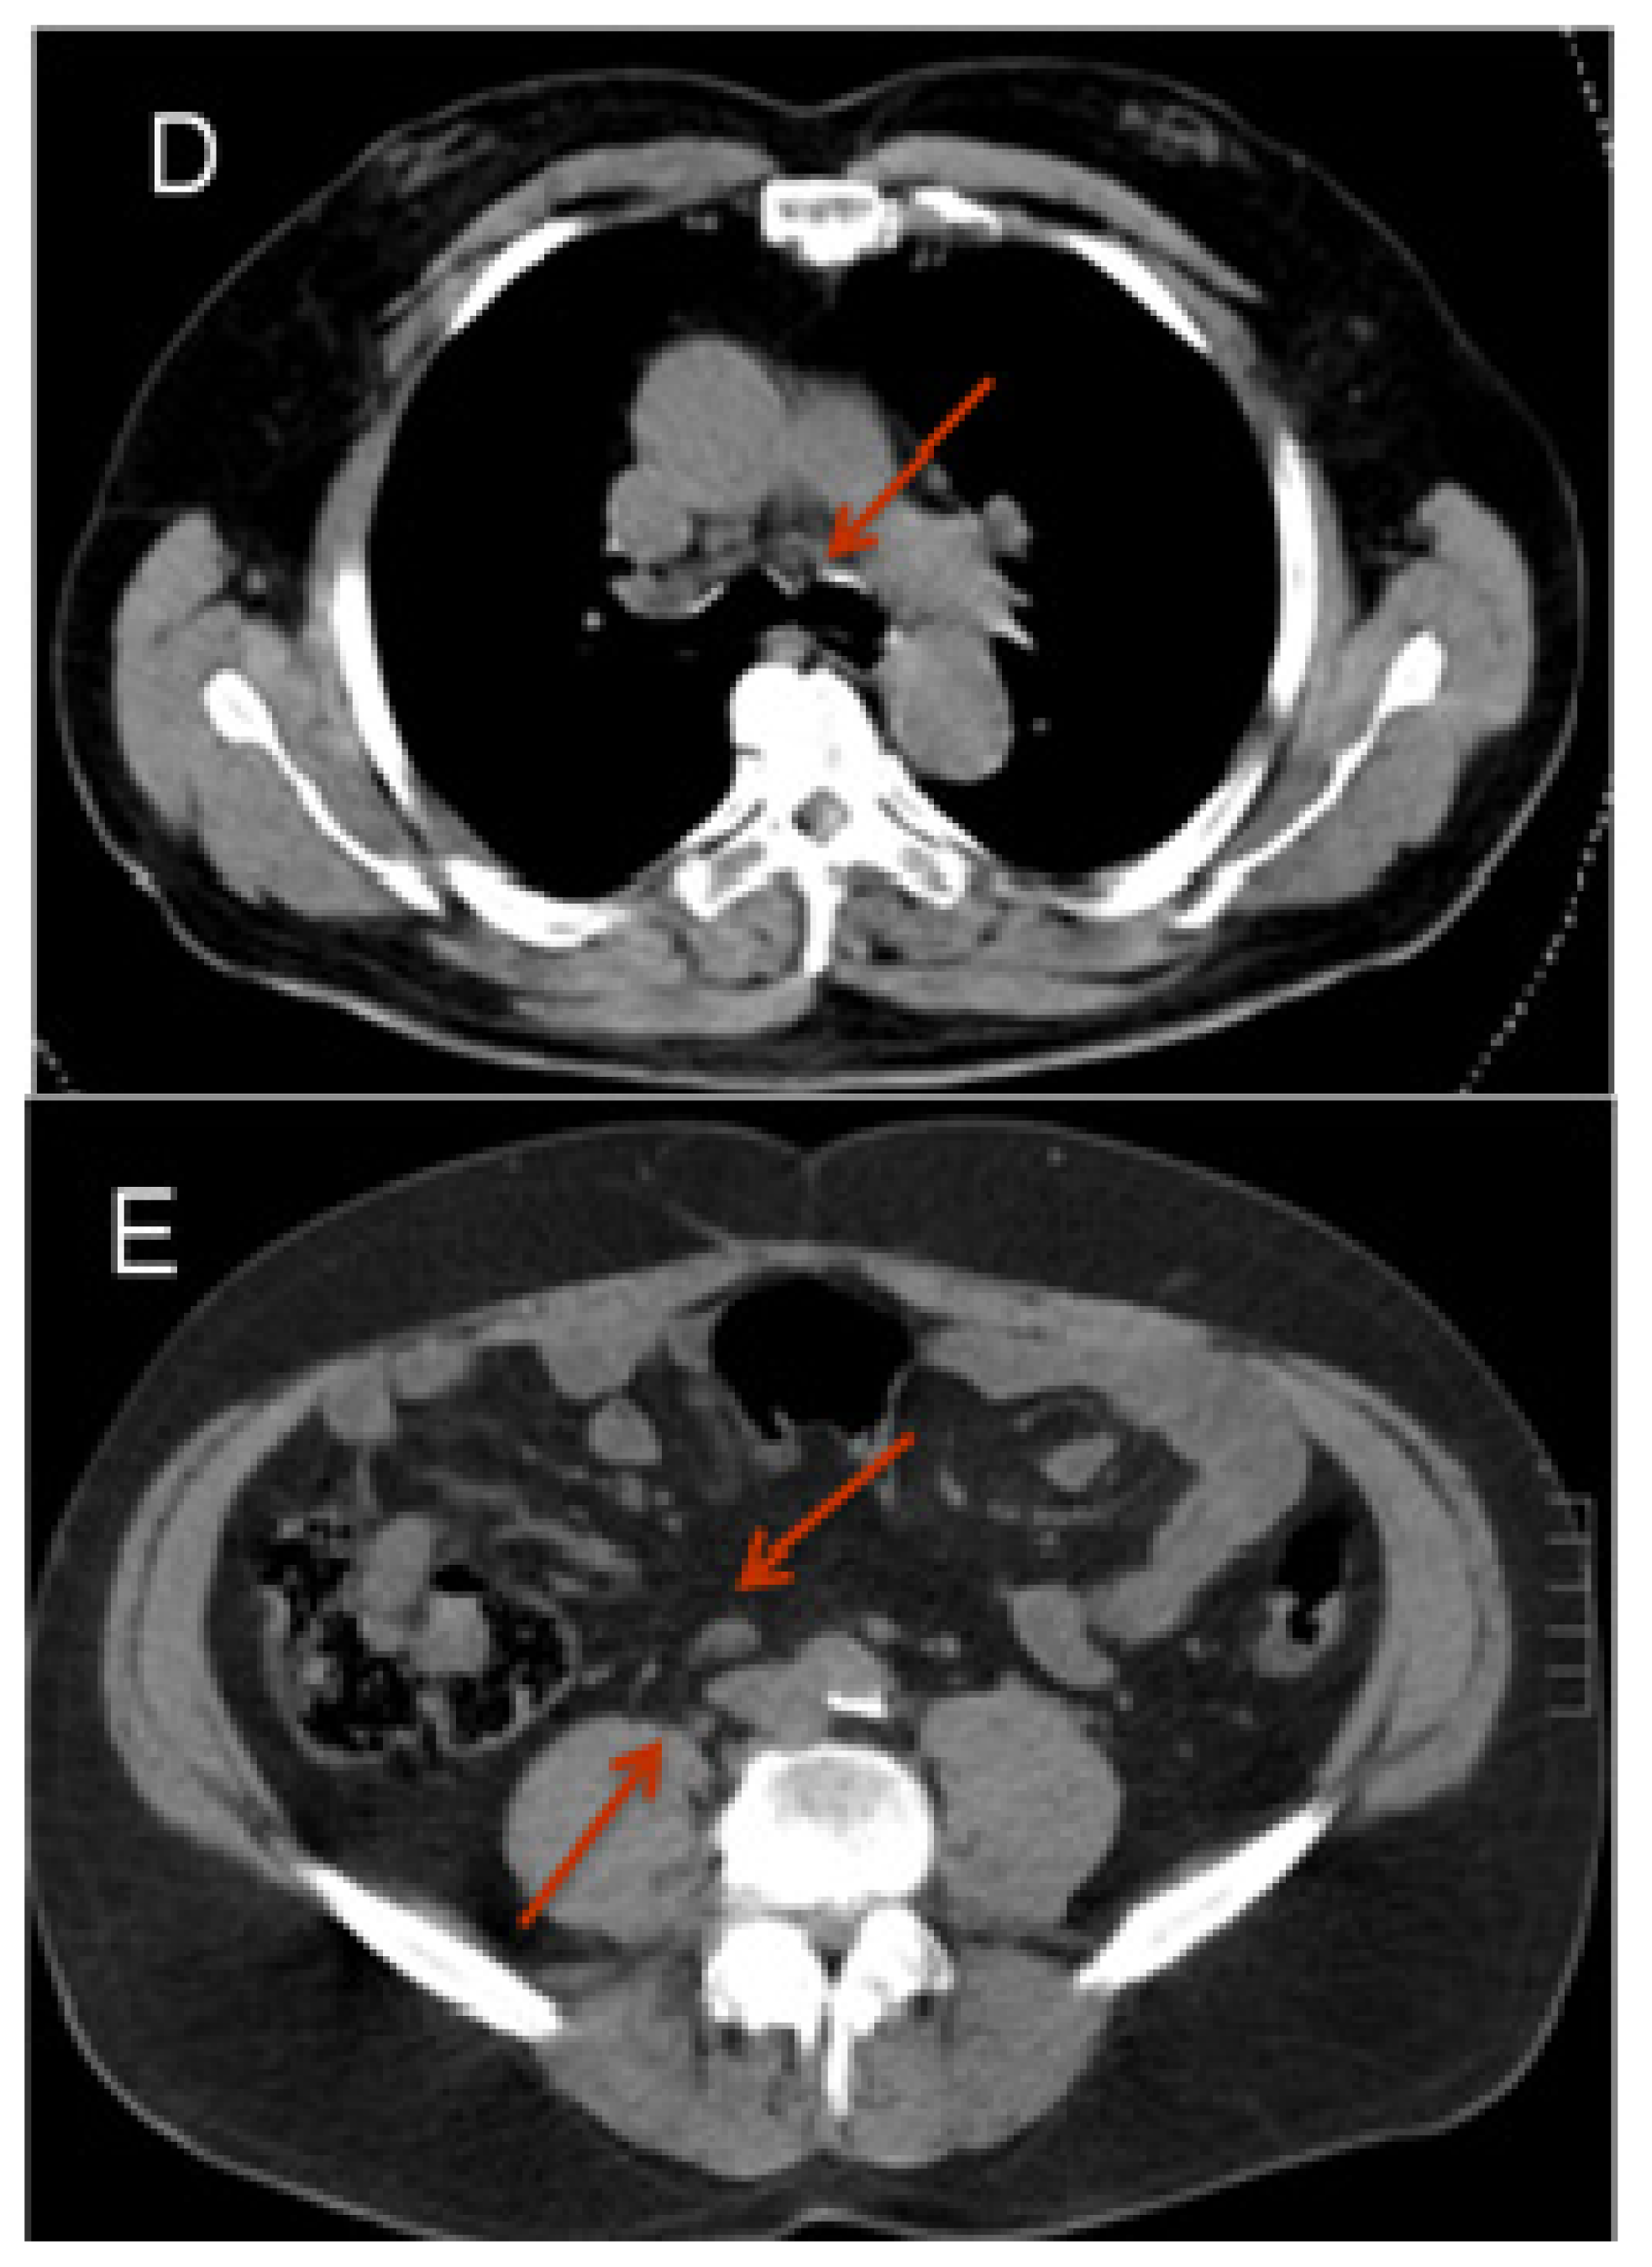

- Afshar-Oromich, A.; Malcher, A.; Eder, M.; Eisenhut, M.; Linhart, H.G.; Hadaschikc, B.A.; Holland-Letz, T.; Giesel, F.L.; Kratochwil, C.; Haufe, S.; et al. Pet imaging with a [68GA] gallium-labelled PSMA ligand for the diagnosis of prostate cancer: biodistribution in humans and first evaluation of tumour lesions. Eur. J. Nucl. Med. Mol. Imaging 2013, 40, 486–495. [Google Scholar]